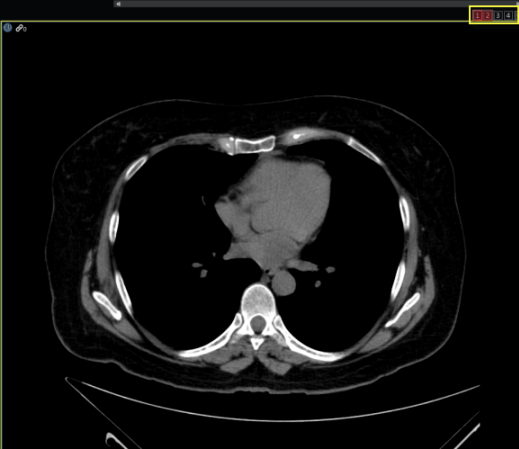

All Study

When this option is selected along with the Grids matrix layout, the viewer will load all open studies (current and prior) into available image frames. If there are too many images for the number of frames available, a virtual monitor will appear in the top right corner of the image frame in order to accommodate the images. These are shown highlighted in yellow in the image below. The selected virtual monitor is highlighted red.

Note: A macro shortcut can be created to enable switching back and forth between the virtual monitors.